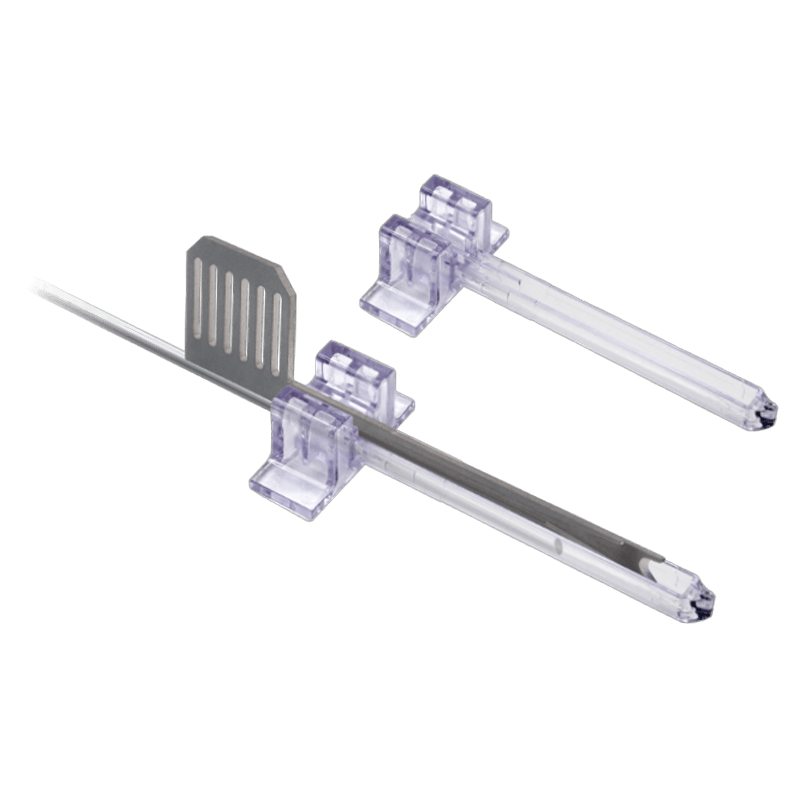

Surgical and Medical Instruments

Surgical and Medical Instruments

View our endoscopic soft tissue release system.

Instruments